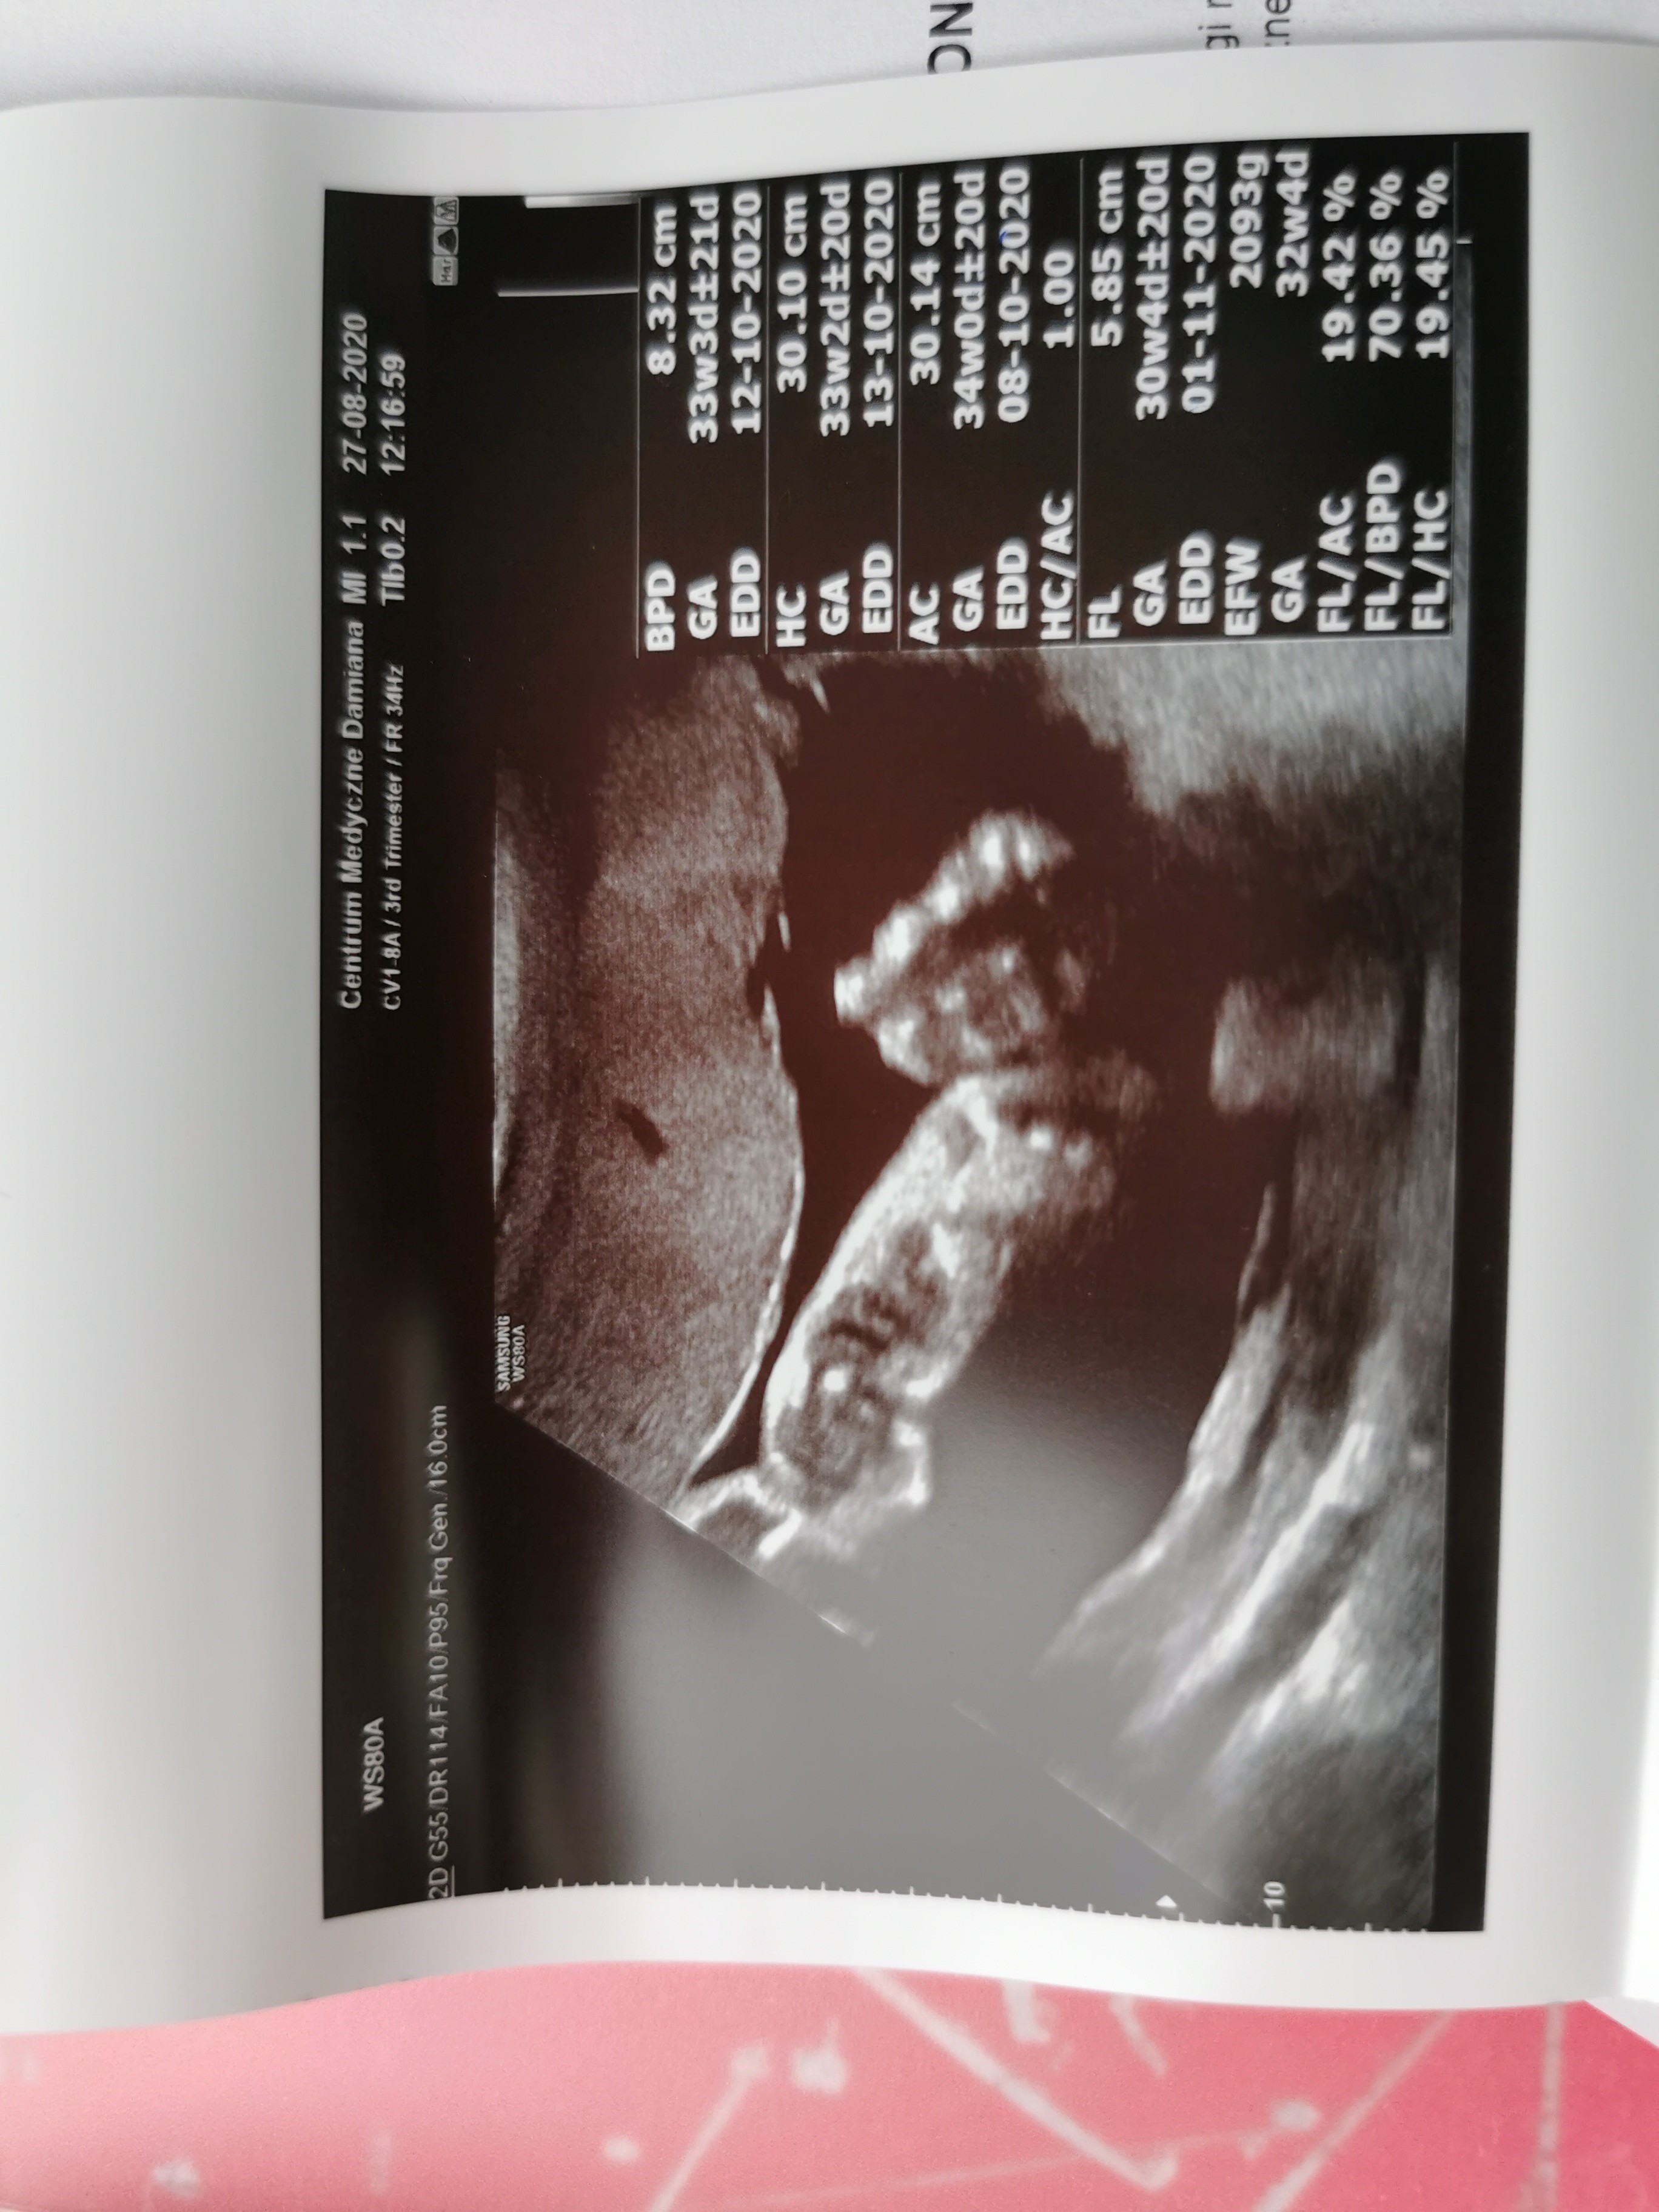

U nas wszystko dobrze😊dziś miałam usg 3.trymestru. Termin wyliczony od daty transferu to początek listopada, a z usg wychodzi już 17.10...Oskar szybko rośnie 😊aktualnie ma 2093g😍Jedyne do czego można się przyczepić, to leży sobie głową do góry... Taki gość. Załączam sweet focię stópki i piąstki. Widzę, że sporo jest nowych osób na forum, więc dla tych co nie wiedzą, to będzie nasze drugie invitrowe dziecię. Licząc od poprzedniego porodu, udał się dopiero piąty transfer. Naprawdę warto próbować do skutku!!! ❤️🥰😘POZDRAWIAMY!!!